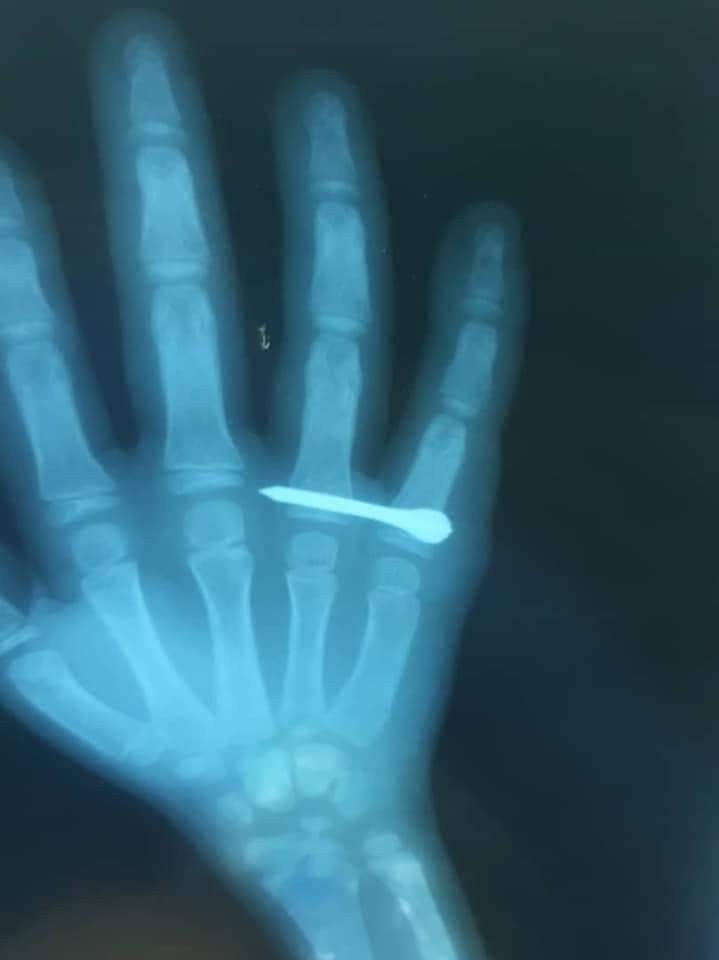

Esad rejiminin İdlib’e düzenlediği hava saldırısında kullandığı çivili bomba küçük bir çocuğu yaraladı.

Esad rejimi, gerilimi azaltma bölgesi ilan edilen İdlib’e hava saldırı düzenlemeye devam ediyor. Pazartesi akşamı düzenlenen hava saldırısında Heş köyü C5 füzeleriyle hedef alındı. Füzelerin çivili bombaya sahip olması nedeniyle etrafa çok sayıda çivi saçıldı. Etrafa yayılan çivilerden birisi küçük bir çocuğun eline saplanırken, küçük çocuk bölgede bulunan sahra hastanesine nakledildi.